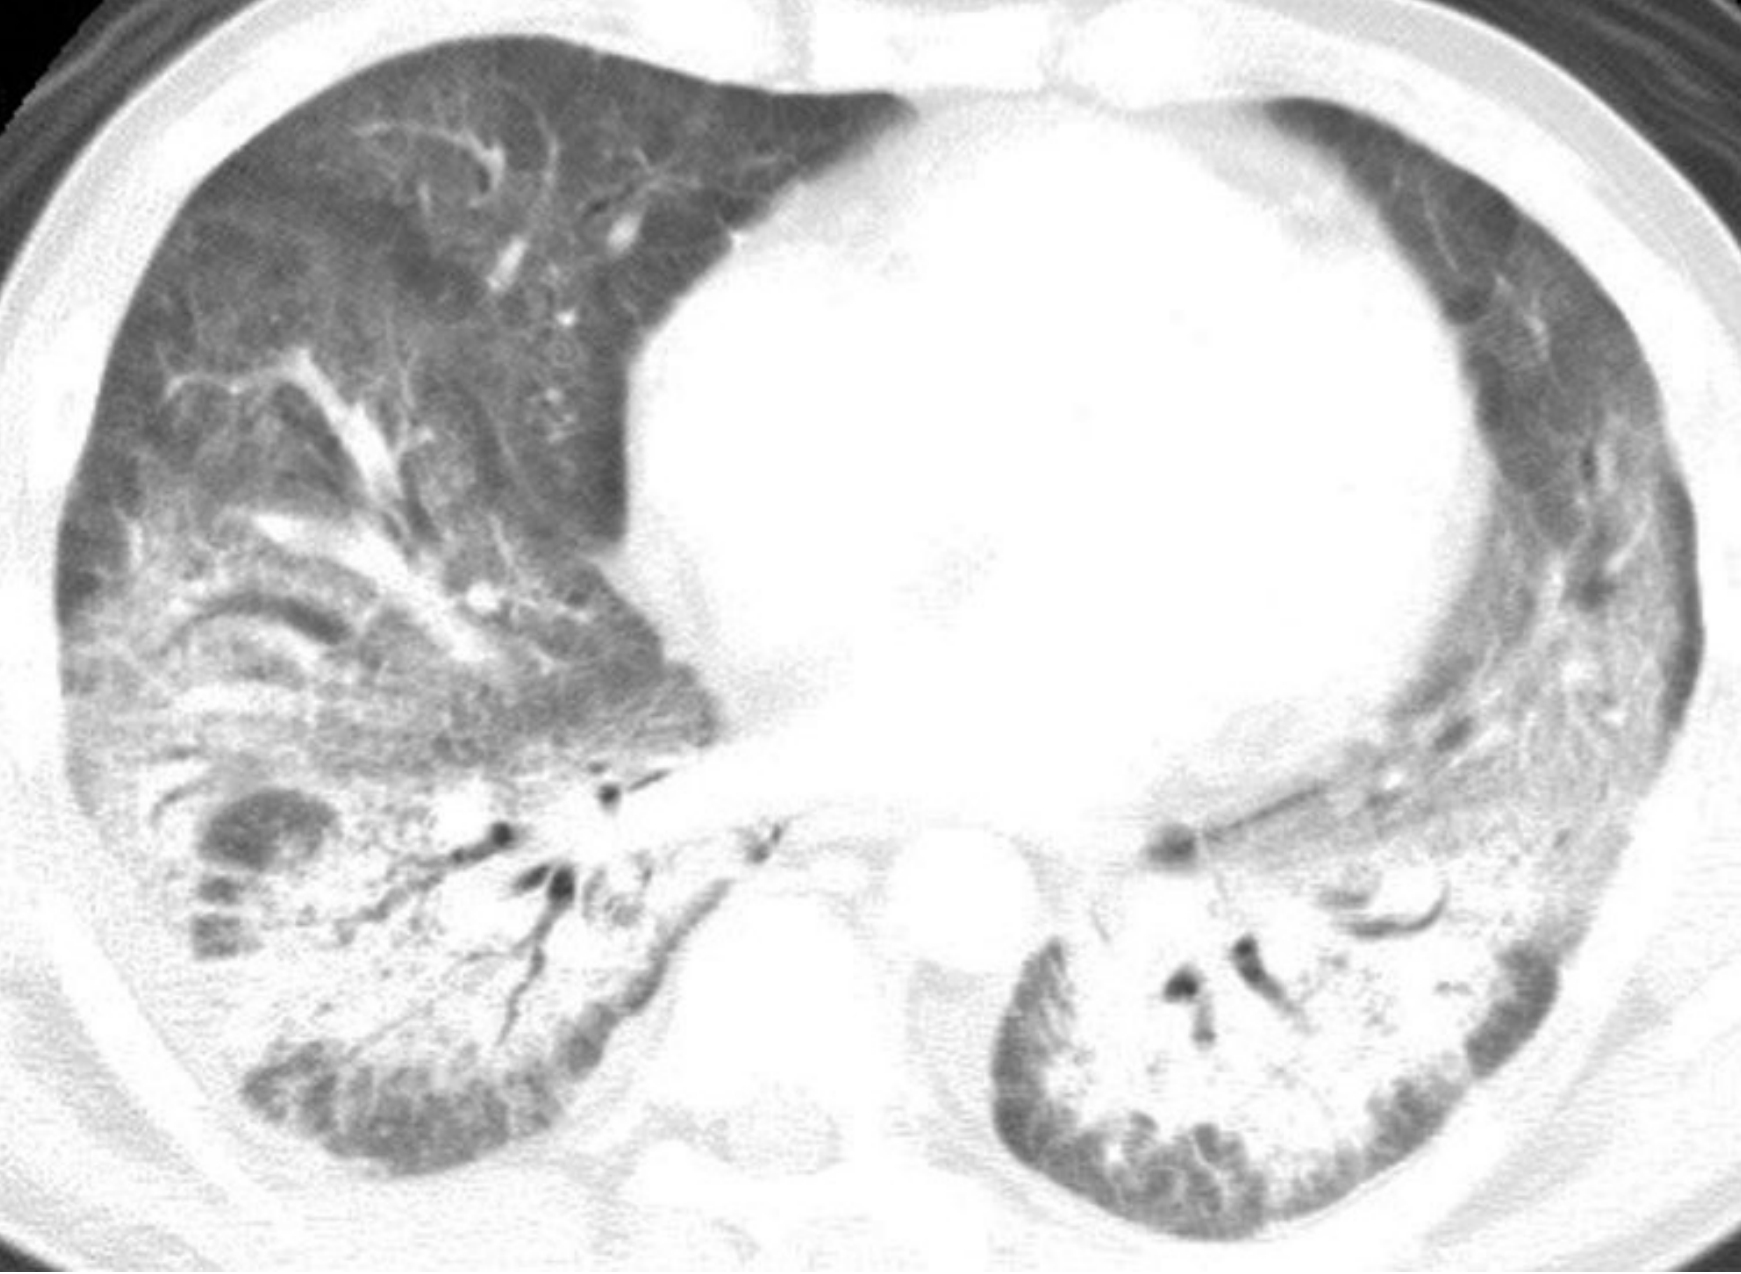

HRCT上异常病变的分布特点有助于区分不同类型的间质性肺炎及鉴别间质性肺炎与其他弥漫性肺部疾病。普通型间质性肺炎、非特异性间质性肺炎及脱屑性间质性肺炎主要表现为肺外周分布为主的异常,累及肺底和肋隔角其余类型的间质性肺炎典型表现为同等累及肺外周部与中央部。其他病因导致的弥漫性肺部疾病(如过敏性肺炎或结节病)通常呈弥漫或中心轴分布,下肋膈角不受累。

d9aa28845b7cba2a1759d5760b020659.png

异常病变的HRCT分布特征在诊断中的价值。

A.纤维型非特异性间质性肺炎相关的硬皮病患者,HRCT显示以肺外周及胸膜下区分布为主的异常表现;

B.结节病患者,HRCT异常表现主要分布在肺门区及支气管周围,而相对未累及胸膜下区。对于慢性症状的病例,胸膜下及肺基底部分布为主的病变提示普通型间质性肺炎、非特异性间质性肺炎或脱屑性间质性肺炎。弥漫性或者中心轴分布是间质性肺炎的不典型分布,提示其他疾病,如过敏性肺炎或结节病。